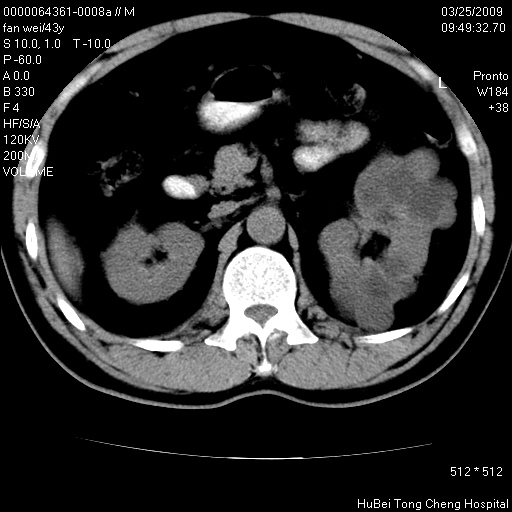

患者 男,43岁。左侧腰部不适两天。平素健康。无家族遗传病史。

腹部彩超提示:1)轻度脂肪肝。2)左肾多发囊性占位性病变;建议行进一步检查。

临床诊断:左肾多发囊性占位性病变,性质待定(多发肾囊肿?)。

双肾ct轴位平扫+增强扫描(层厚10mm,螺距1.0,重建间隔10mm),图像如下:

多囊肾的影像诊断标准:有阳性家族史,年龄<30岁,单侧或双侧肾脏有两个肾囊肿;30~59岁,两侧肾脏各有两个肾囊肿;60岁以上,每侧肾脏有4个囊肿。敏感性和特异性达86%和80%。

此病例影像诊断符合,要结合家族史,腰痛、血尿、尿路感染史,有无高血压等综合判断,如无相应的临床症状,本身病变也无意义了(个人观点)

左肾体积变大,支持多囊肾。

囊肿数得清,肾功能正常,考虑多发肾囊肿.另外,右肾后极突向肾周间隙的那个病灶是不是错构瘤,请楼主调窗看看.